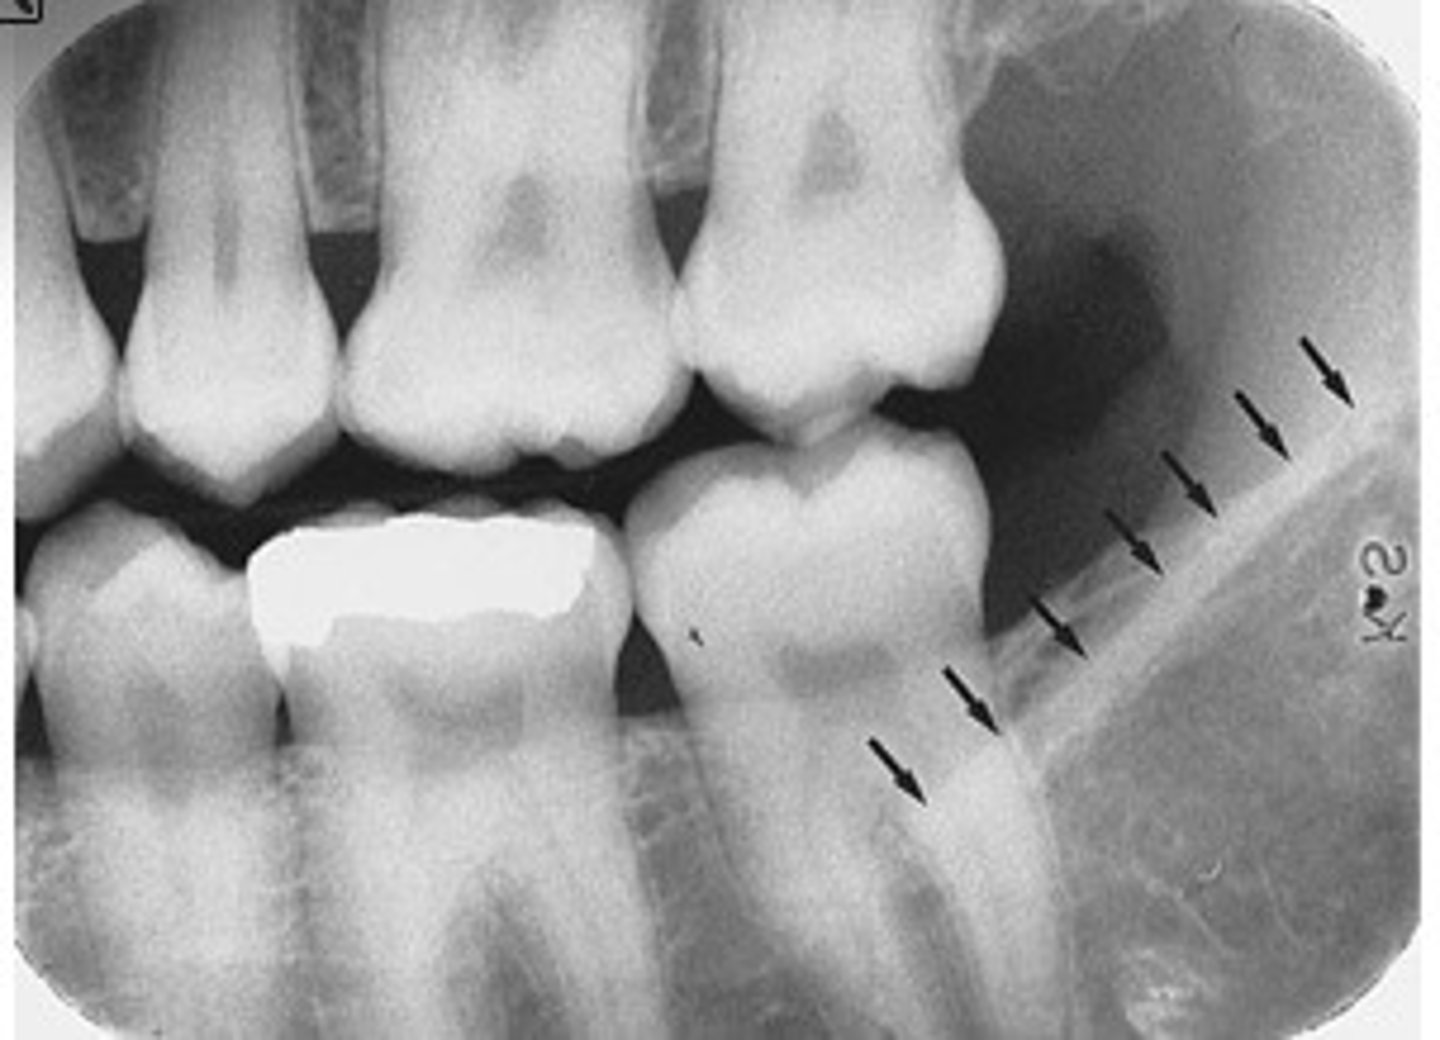

what is this?

what is this radiolucent area in the image?